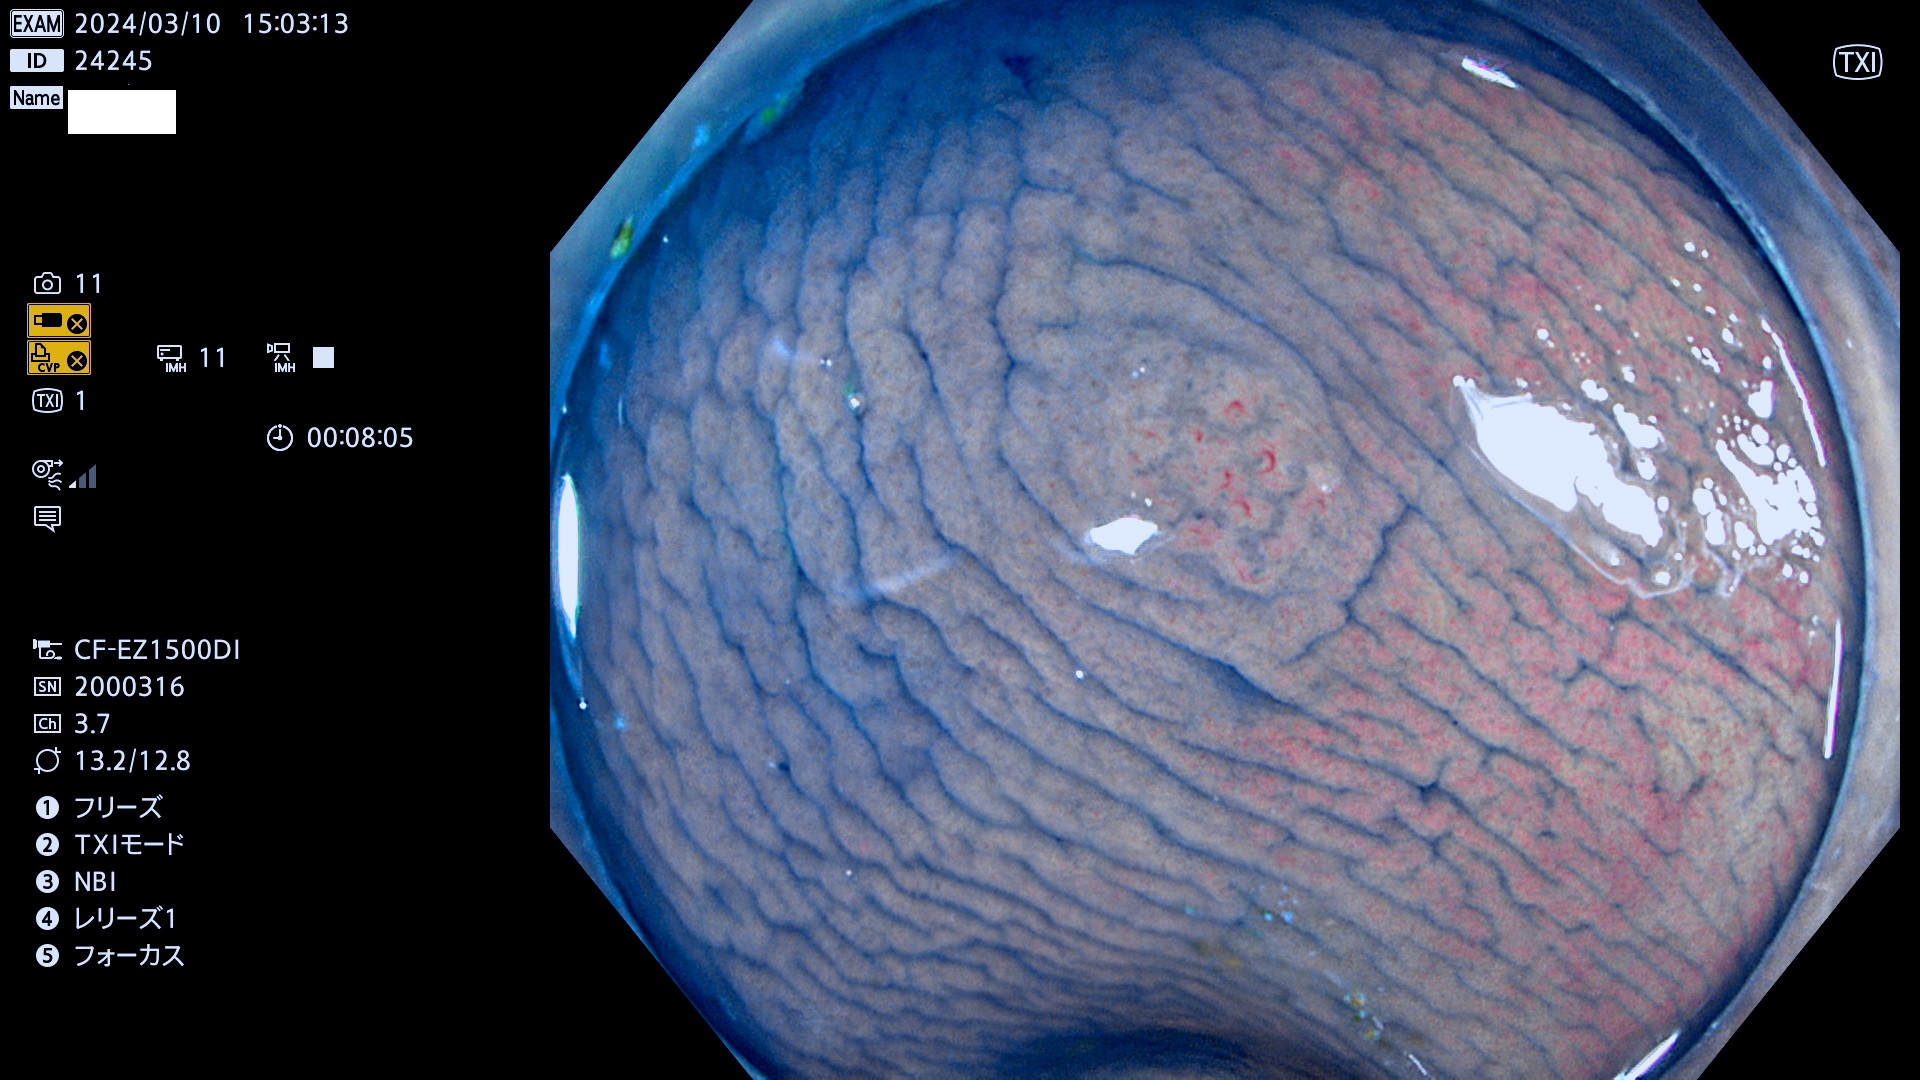

今週のUb、Uc型腺腫

表面型腺腫(Flat Adenoma)の中で、完全に平坦な物をUb、陥凹している物をUcと呼びます。平坦隆起型(Ua)よりも、発見が難しく危険な病変です。

毎週の検査(木・金・土・日)に発見されたUb、Uc型・腺腫を、その週の日曜の夜にUPし1週間、提示します。

抽出の対象期間 2024年3月7日(木)〜3月10(日)の4日間(40件の検査)6件 (6/40=13%)